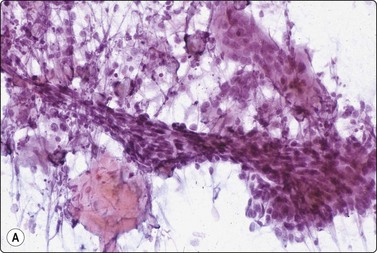

Squamous cell carcinoma (Fig. 14.13)

Scrape smears are a simple way of diagnosing squamous cell carcinoma of the skin, particularly ulcerated lesions. Inflammatory crust and any surface keratinous layers must first be carefully removed to obtain diagnostic cells from the deeper layers. The technique is described above. Nodular and deeply invasive tumors and recurrences are better examined by FNB.

image image

Fig. 14.13 Squamous cell carcinoma

(A) Aggregate of pleomorphic, obviously malignant cells with dense squamoid cytoplasm and distinct cell borders; no obvious keratinization in this field; FNB smear from ulcerated 10–15-mm tumor lower lip (MGG, HP); (B) Cohesive tissue fragment of malignant squamous epithelial cells; scrape smear from ulcerated skin tumor (Pap, HP).

Cytological criteria of squamous cell carcinoma are described in several other chapters, mainly in Chapter 8. The differential diagnosis between well-differentiated squamous carcinoma with cystic degeneration and branchial and other benign cysts lined by squamous epithelium can cause problems due to subtle squamous cell atypia in the former and reactive atypia and metaplasia in the latter (see Chapter 4). Distinction between keratotic basal cell carcinoma and basaloid squamous cell carcinoma can be difficult.4 Cytological criteria for basal cell carcinoma are listed below. The cytomorphology of adenoid (acantholytic) squamous cell carcinoma can cause problems.44 Distinction between in situ (dysplastic solar keratosis, Bowen’s disease) and superficially invasive carcinoma is not possible in smears.